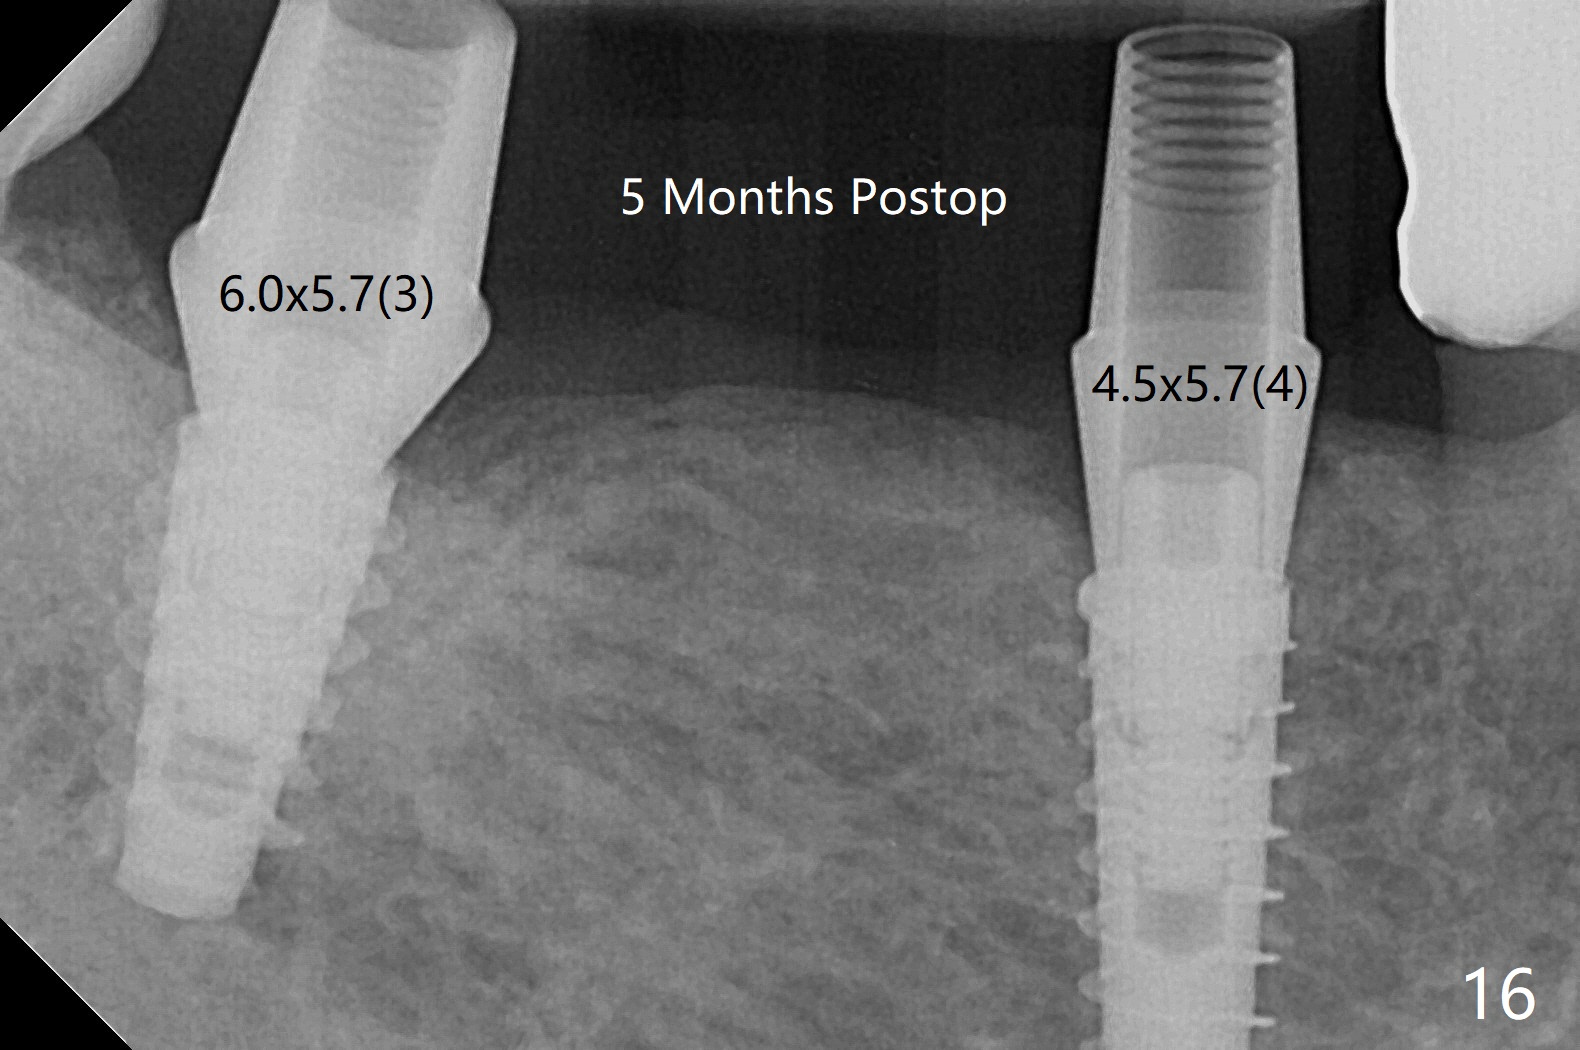

The extraction socket of #31 has a thin septum (Fig.2), which is removed partially with 12 mm bone trimmer (Fig.3). After placement of a 5x9 mm FC implant (~40 Ncm) and 6 mm bone profile drill, a 5.5x4(2) mm abutment is incompletely seated (Fig.5 <) and later is changed to a 4.5x1 mm temporary abutment (Fig.6, 8 T). The latter is used to fabricate a provisional, which in turn supports the distal papilla (Fig.8 *). The gingiva is slightly erythematous immediately post periodontal dressing removal (3 weeks postop, Fig.9). Take CT to confirm whether the cortical drill helps keep the #29 implant lingual. Use a profile drill at #29 if crestal bone loss is not obvious. There is bone coronal to #29 implant 4 months postop (Fig.10). Upon incision, the ridge is rounded (Fig.10'), but the implant appears to be buccally placed (Fig.10'' (post high speed handpiece and 5.5 mm profile drill)). The latter is confirmed by CT (Fig.12, as compared to design (Fig.11)). In spite of use of cortical drill coronally, the implant is still deviated buccally due to contrasting deferential bone density linguobuccally (Fig.13). By comparison, there is no such bone density differential involving an immediate implant at #31; the implant is placed in the socket without contacting the buccal or lingual cortices (Fig.14). The final implant is the same as expected (Fig.15). To avoid implant deviation in the lower premolar region, leave the root in place until osteotomy is finished. Five months postop, the temporary and healing abutments at #31 and 29 change to pair ones (Fig.16). Since there is limited clearance from the crestal bone, smaller abutments are used with the apparently same degree of seating (Fig.17). The abutments are prepared due to the mesial (#31) and buccal (29) tilt before impression.